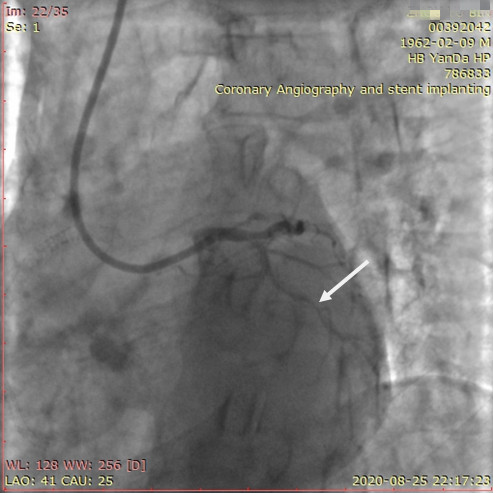

李先生蜘蛛位術前影像

李先生蜘蛛位術后影像

術前,翟光耀主任還親自為李先生復查冠狀動脈造影,造影結果顯示:患者的前降支、回旋支、右冠等冠脈三支嚴重病變、嚴重鈣化,且均為彌漫性長病變,最重處99%以上管腔極嚴重狹窄。翟主任仔細閱讀造影結果后指出:結合李先生的實際情況,雖然微創介入手術難度比較大,但仍可行;李先生心臟三支主干動脈均存在極其嚴重的狹窄,每一支動脈均至少植入2-3枚支架,根據患者的耐受情況,李先生可能需要分3次分別對三支動脈進行介入手術;考慮到李先生路途遙遠,病情嚴重,不宜反復奔波,并且患者迫切要求能夠徹 底解決病痛,在病情允許的情況下,如果手術順利,爭取為患者進行“一站式”手術,一 次 性解決全部三支動脈病變!

手術方案確定之后,在心血管內三科趙景新主任、介入醫學科富孝晨主任的配合下,翟光耀主任親自擔任主刀,分別依次對李先生的三支動脈進行了完全血運重建。由于手術進展順利,李先生術中沒有任何癥狀,耐受良好,于是成功的將三支動脈“一站式”治療!術中,由于李先生左主干遠端分叉處存在嚴重病變,翟光耀主任選擇國際指南推薦的DK-mini-Crush技術,確保了分叉處兩支主干開口均萬無一失。據悉,DK-mini-Crush技術是目前冠脈分叉病變領域最為復雜及難以掌握的介入技術之一,對手術醫生經驗、體力均提出了極大的挑戰。極為擅長復雜介入技術的翟光耀主任卻用嫻熟的技術確保了李先生手術的成功。

冠狀動脈嚴重鈣化合并狹窄病變是冠脈介入的一大難題,血運重建難度大,成功率低,并發癥發生率高,該例患者的成功救治標志著我院冠脈介入水平又躍上了一個新的臺階。